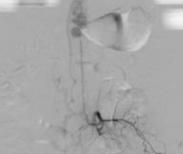

• 脊髓血管畸形

628健康網為您分享有關脊髓血管畸形的癥狀,脊髓血管畸形的治療方法,脊髓血管畸形的預防知識,脊髓血管畸形的癥狀圖片,脊...